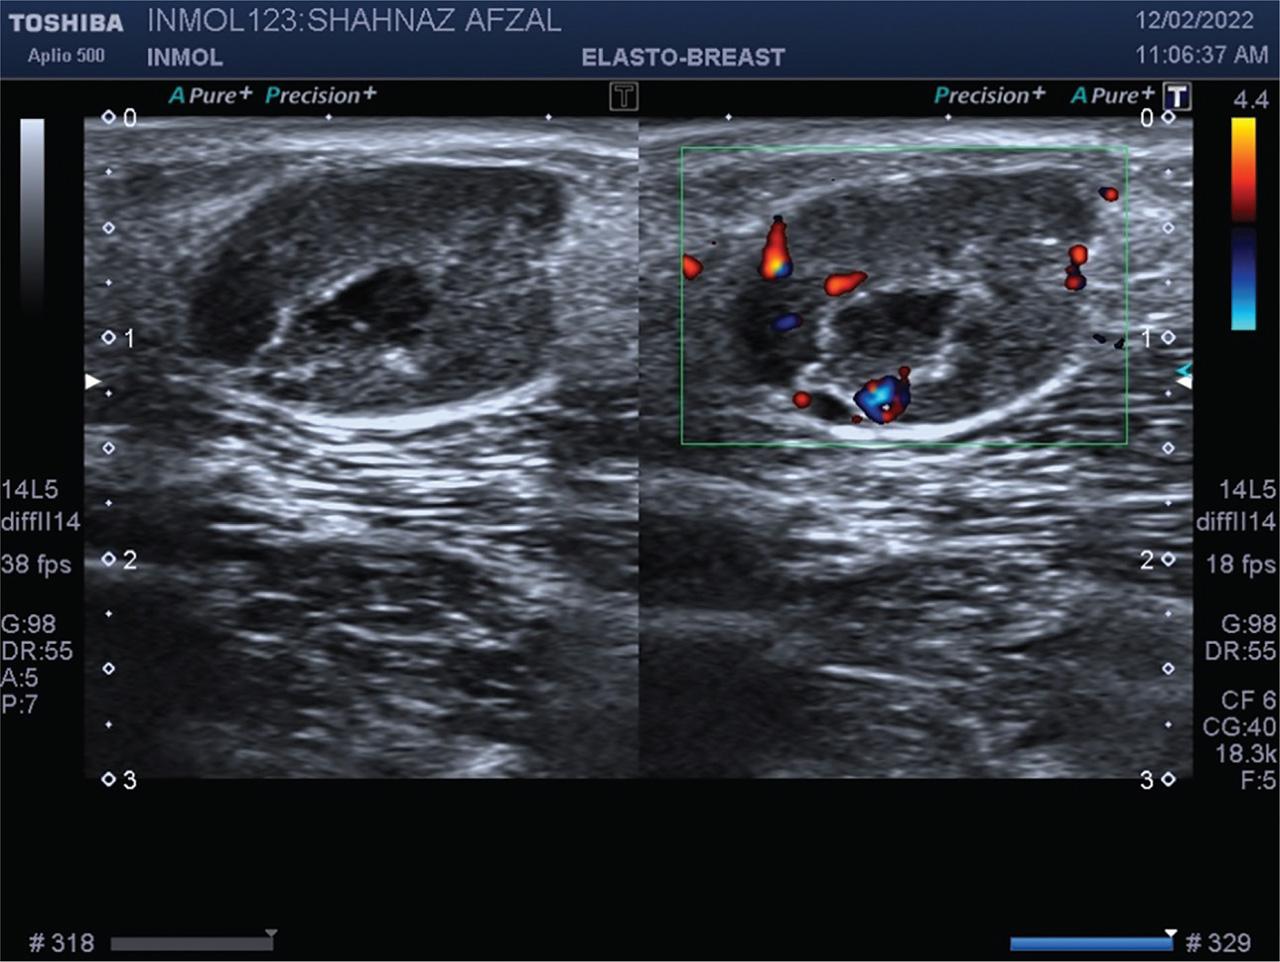

USG of cutaneous nodule revealed a 20 ×12 mm lobulated heterogeneous echogenicity lesion with internal necrotic changes in the subcutaneous plane of right axillary region, showing significant vascularity on color Doppler evaluation. USG, ultrasonography.